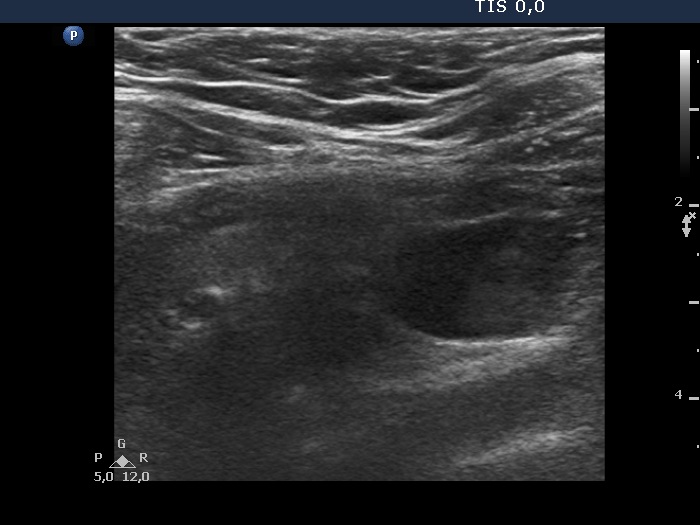

Parathyroid lesions - case 742 (ultrasonographic picture 4)

Left lobe, longitudinal view. It was impossible to place the transducer on the patient's neck so that both the thyroid gland (upper, i.e. left in the image) and the parathyroid gland (lower, i.e. right in the image could be well represented.